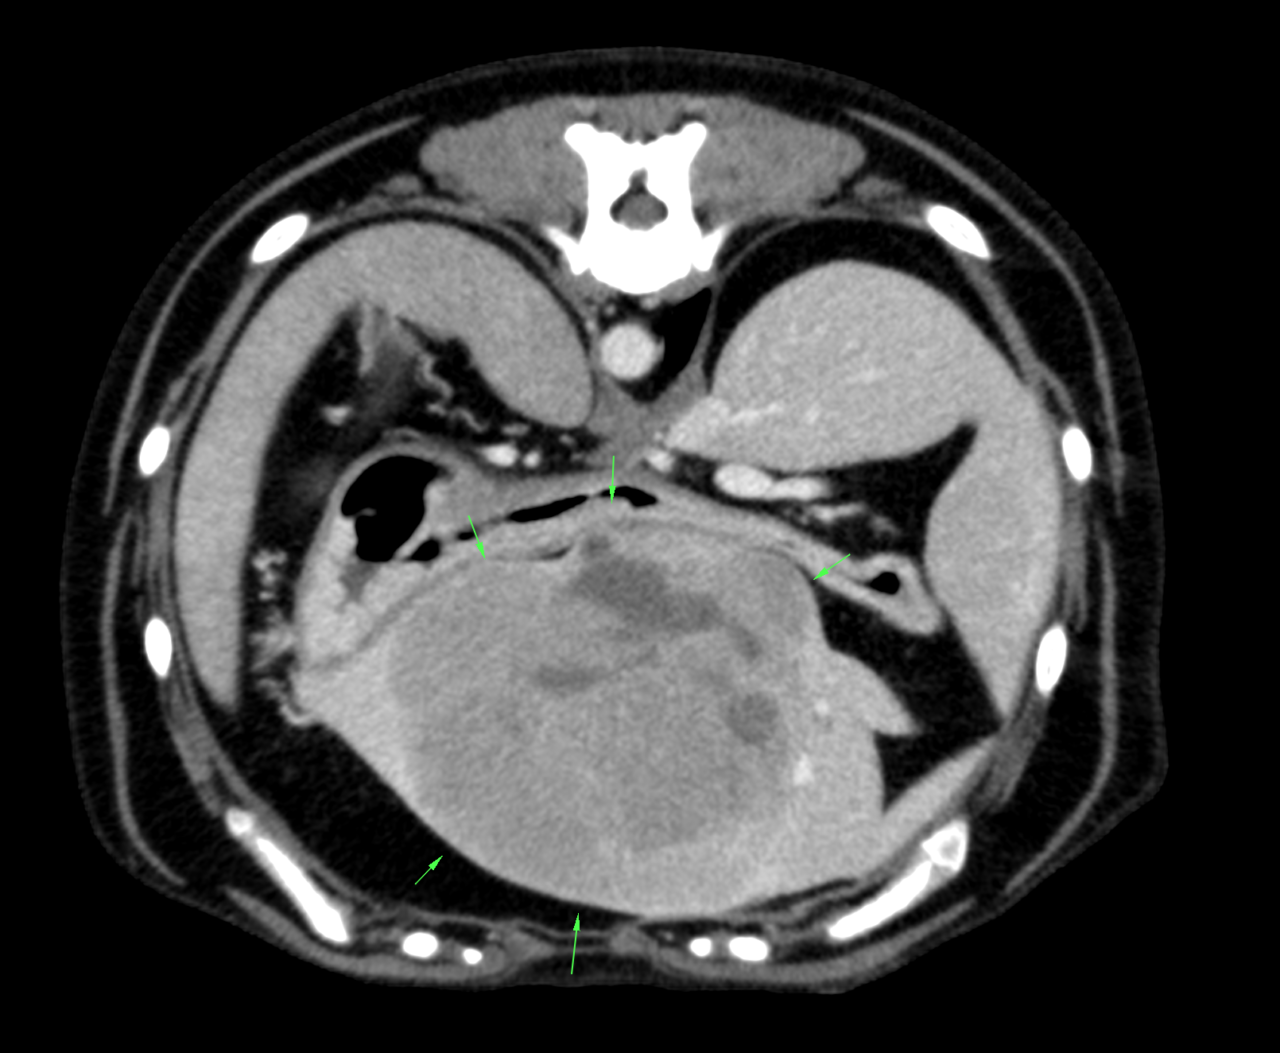

大型犬が高齢期を迎えたので、かかりつけ医で健康診断を実施した所、超音波検査で肝臓に腫瘍が発見されました。症状はなく元気に過ごしているとの事。特に高齢犬の場合、内臓の病気が進行する前に見つかれば、治療や予防措置を早めに取ることができます。 犬は痛みや不調を隠す傾向があります。健康診断を通じて、飼い主が気づかない微細なサインや異常を検出できるため、愛犬が快適に過ごせるようサポートできます。特に6歳以上の大型犬には、健康管理が重要です。健康診断で、肝機能や腎機能などの数値を確認し、栄養管理や生活習慣を見直すきっかけにしましょう。健康診断は、愛犬の長生きとクオリティ・オブ・ライフ(QOL)を向上させるために不可欠です。この患者さんはCT検査で外科的な対応が可能と判断され無症状のうちに肝臓腫瘍の摘出術が行われました。